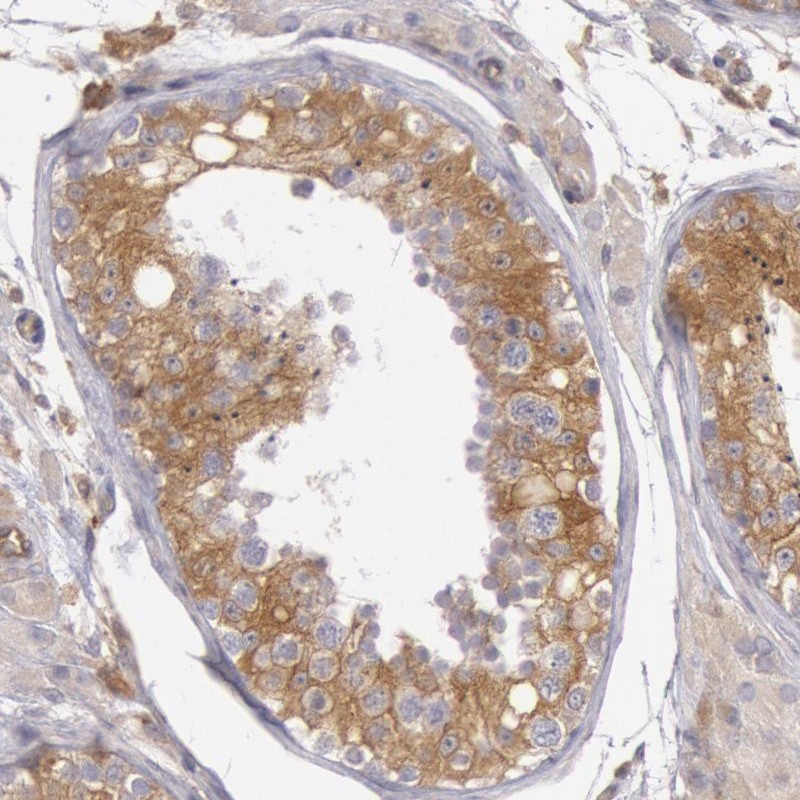

Immunohistochemical staining of human testis shows moderate cytoplasmic positivity in cells in seminiferus ducts.